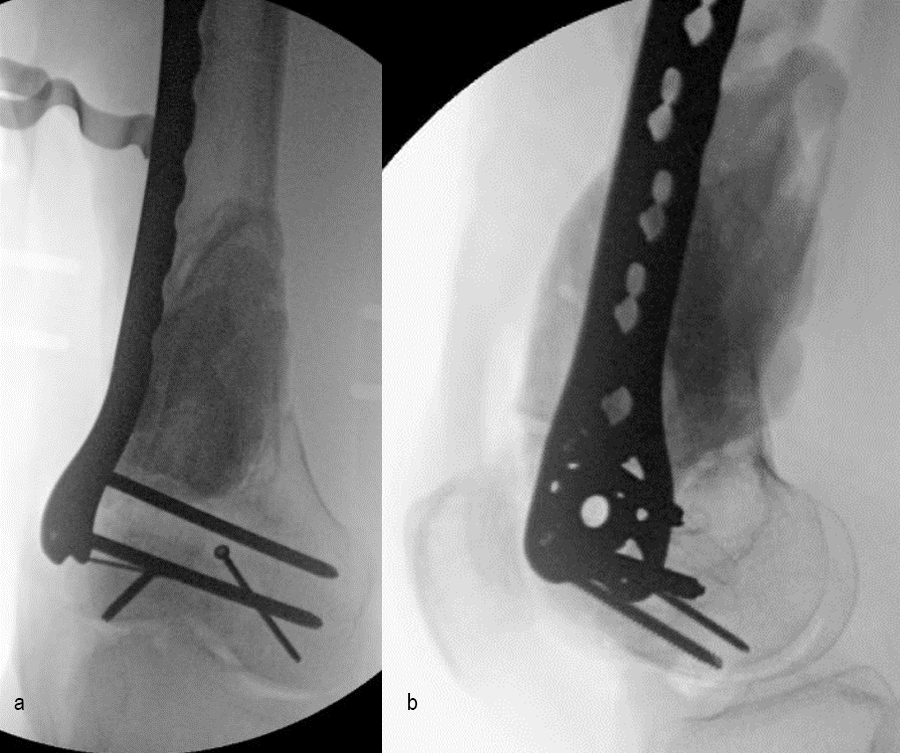

At 5 days post-initial surgery, the lung injury was improved, so the patient underwent open reduction and internal fixation (ORIF) of the right distal femur with resection of devitalized bone and cement spacer placement (Fig 7). Definitive fixation of the other fractures (ankle and ribs) was undertaken over time.

Following the advent of Covid-19 in early 2020, the patient was lost to follow-up for almost one year and was eventually seen again in December 2020 (Fig 8). At this follow-up, a CT scan was planned for the right distal femur and a graft cage ordered. Surgery was scheduled for early 2021.

At the 3-week follow-up (post-graft cage, Fig 12), the patient’s wounds were healthy. He had a range of motion (ROM) of 0–80 in his right knee. He was allowed weight bearing as tolerated (WBAT) with crutches.